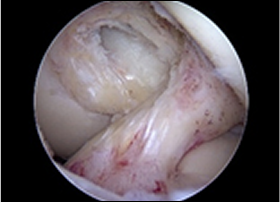

치료 전 붉게 패여 손상된 연골이 치료 후 정상적으로 회복된 모습

before img after img